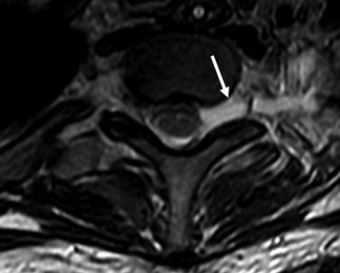

(Справа) MPT (Т2 ВИ FS), аксиальная проекция: визуализируется шваннома ПС, связанная с корешком. УЗИ позволяет идентифицировать опухоль и отличить ее от лимфоузлов, чаще встречающихся в этой области. (Слева) УЗИ, поперечная проекция: визуализируется солидная гипоэхогенная опухоль с задним усилением, лежащая между передней и средней лестничными мышцами. Расположение в перивертебральном пространстве и УЗ-картина являются диагностическими признаками шванномы ПС.

МРТ шейного отдела позвоночника. Аксиальная Т2-взвешенная МРТ. Псевдоменингоцеле.